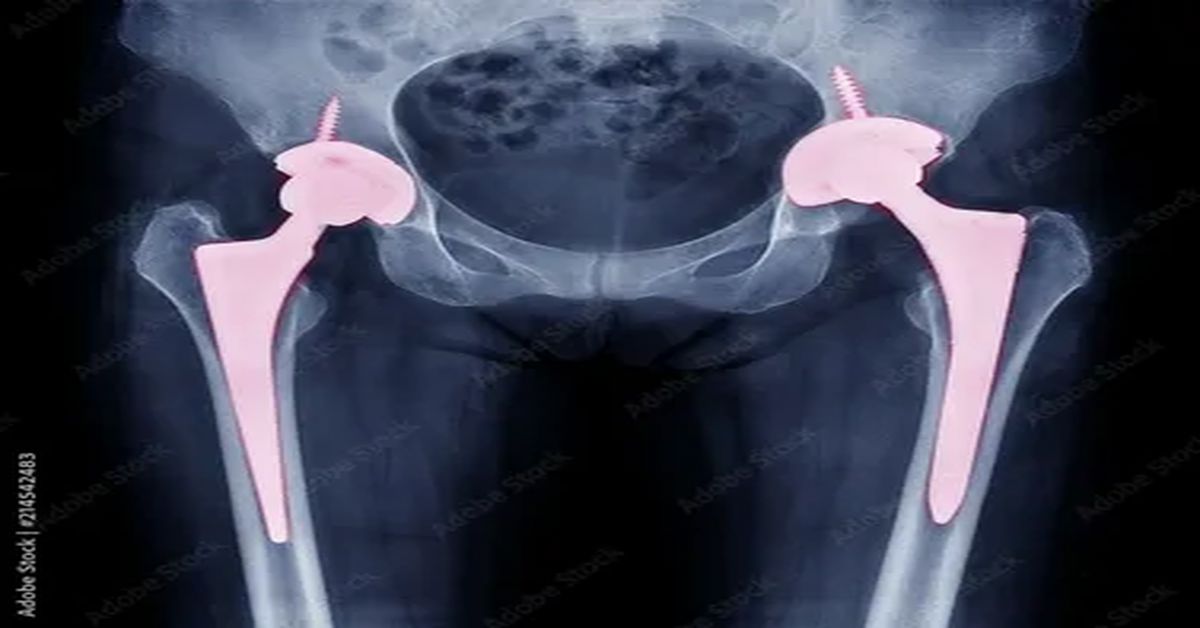

total kalça protezi birinci tür kalça eklemindeki eklem yuvası yapay malzemelerle değiştirilir. Total protezler, eklem deformasyonu olan hastalar için uygundur. Bu sayede hem ağrı azalır hem de eklem hareketliliği önemli ölçüde artar.

Parsiyel protez, sadece hasarlı femur başını değiştirmek amacıyla uygulanır. Genellikle yaşlı hastalarda , ameliyat süresini kısaltır ve iyileşme sürecini hızlandırır. Ayrıca kemik dokusunun büyük kısmı korunmuş olur, bu da uzun vadede avantaj sağlar.

Yüzey replasmanı olarak bilinen bir diğer tür, özellikle genç ve aktif hastalar için uygundur. Bu yöntemde femur başının yüzeyi metal bir kaplama ile değiştirilir, eklem yuvası ise büyük ölçüde korunur. Bu sayede ileride tekrar cerrahiye ihtiyaç duyulma olasılığı azalır ve kemik yapısı korunur.

Farklı protez tasarımları arasında malzeme ve şekil farklılıkları da bulunur. Titanyum, seramik ve özel plastik materyallerden yapılan protezler, uzun ömürlü kullanım ve yüksek dayanıklılık sağlar. Cerrahi sonrası fizik tedavi ile eklem fonksiyonu artırılır ve iyileşme süreci desteklenir.